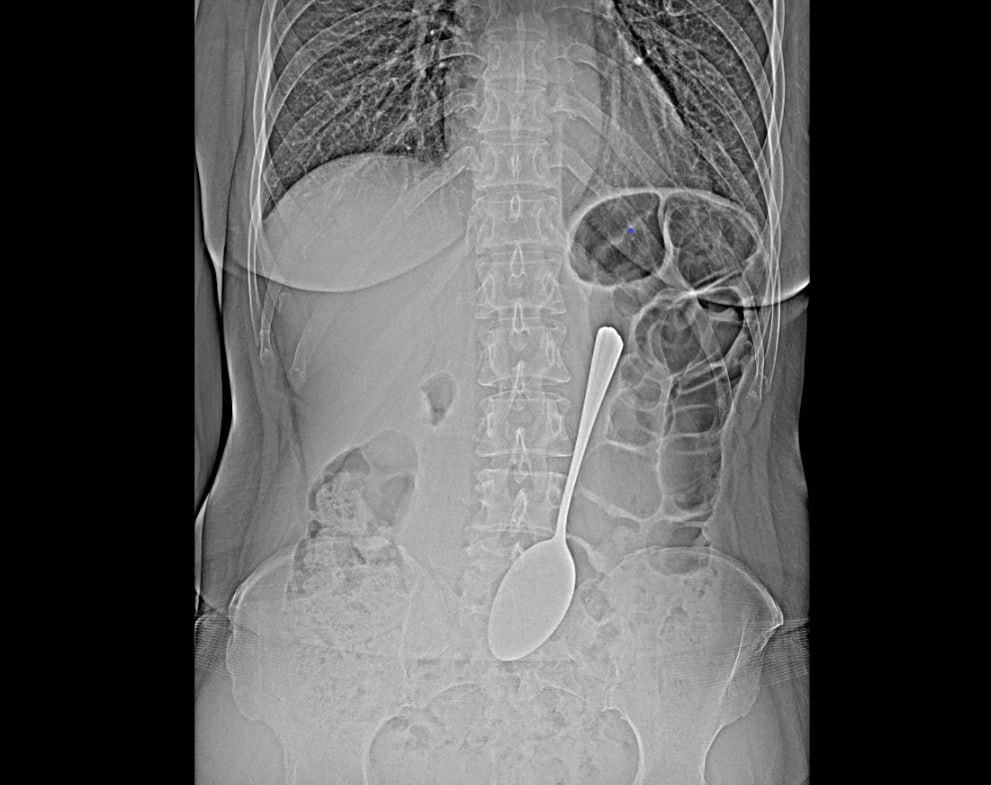

Врачи-эндоскописты БСМП им.В.В.Ангапова спасли женщину, которая проглотила столовую ложку.

Предмет достали из желудка с помощью эндоскопа и соответствующих инструментов, что помогло избежать сложной хирургической операции, сообщили в пресс-службе ведомства.